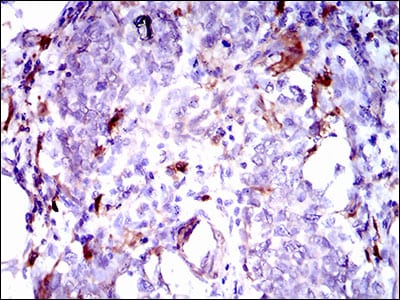

- Immunohistochemical analysis of paraffin-embedded human breast cancer tissues using GPNMB mouse mAb with DAB staining.

- Immunohistochemical analysis of paraffin-embedded human esophagus cancer tissues using GPNMB mouse mAb with DAB staining.